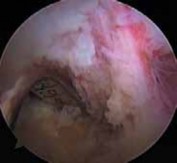

5. If the AL bundle is found to be intact, special care is taken to preserve this bundle while the overlying synovium and ruptured PCL fibers are débrided (

TECH FIG 5A

).

26. Fixation and closure are then performed. TECH FIG 5 • A. An intact AL bundle is preserved and the overlying synovium and ruptured PCL fibers are débrided. B. The exit point for the tibial tunnel along the sloped face of the posterior tibial fossa is just distal and lateral to the intact PCL insertion, as demonstrated by a long 18-gauge bent wire

A B loop.